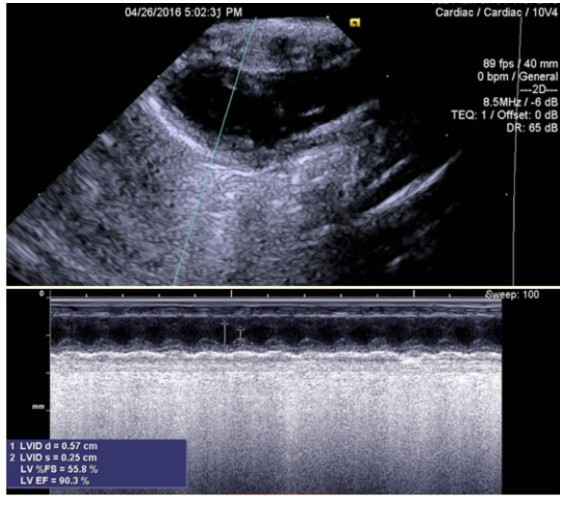

大鼠经胸超声心动图显示经胸超声心动图M型测量左室射血分数和缩短分数

冲击波治疗前后大鼠左心室功能